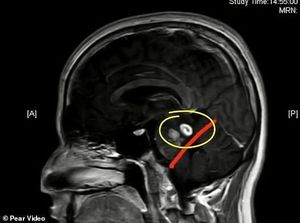

Hiii... Sering Makan Kodok Hidup, Ada Cacing Pita di Otak Pria Ini!

Seorang pria di China mengalami infeksi parasit di otaknya. Hal ini karena ada cacing pita hidup yang bersarang setelah ia menyantap kodok saat kecil!